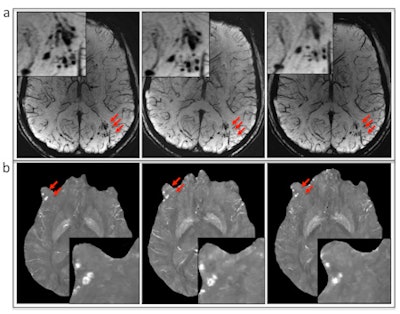

Traditionally, MRI with a T2-weighted gradient-recalled echo (GRE) sequence has been used to determine the number, severity, and size of cerebral microhemorrhages following TBI. However, past research has shown that SWI can provide better sensitivity than GRE, the authors wrote.

Two radiologists independently reviewed the results and agreed on the findings in 41 (95%) of the 43 patients with microhemorrhages. With SWI, they detected 585 microhemorrhages in 37 patients, compared with 362 microhemorrhages at GRE imaging.

SWI also detected significantly more cerebral microhemorrhages per patient (17.7 ± 20.7) than GRE (11.0 ± 12.6). Most microhemorrhages (451/585, or 77%) appeared more conspicuous on SWI than GRE images, and the greatest number of microhemorrhages were found in the frontal subcortical regions (174, or 30%), followed by the parietal subcortical region (87, or 15%) and the temporal subcortical region (79, or 14%).